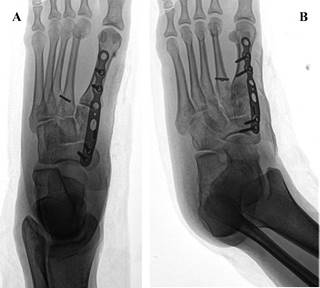

Por un lado, lesiones cuneiformes asociadas a otras fracturas, luxaciones, luxofracturas de una o más cuneiformes adyacentes, han sido previamente descritas.40,41,42 Por otro lado, en trauma complejo de mediopié con lesiones de Lisfranc y compromiso de huesos cuneiformes, en especial la luxación del cuneiforme intermedio, han sido presentadas en forma de reportes aislados de caso (Figura 2 y 3).43,44

Figura 2: Radiografía de pie derecho. A) Proyección anteroposterior; se observa fractura de cuneiforme medial conminuta (flecha corta) y apertura de espacio de Lisfranc (flecha larga). B) Proyección oblicua; se aprecia desplazamiento dorsal de cuneiforme medial (flecha).